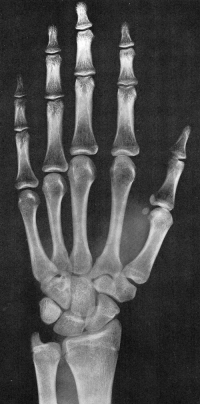

Sexo Masculino

Recém-Nascido

idade óssea - RN